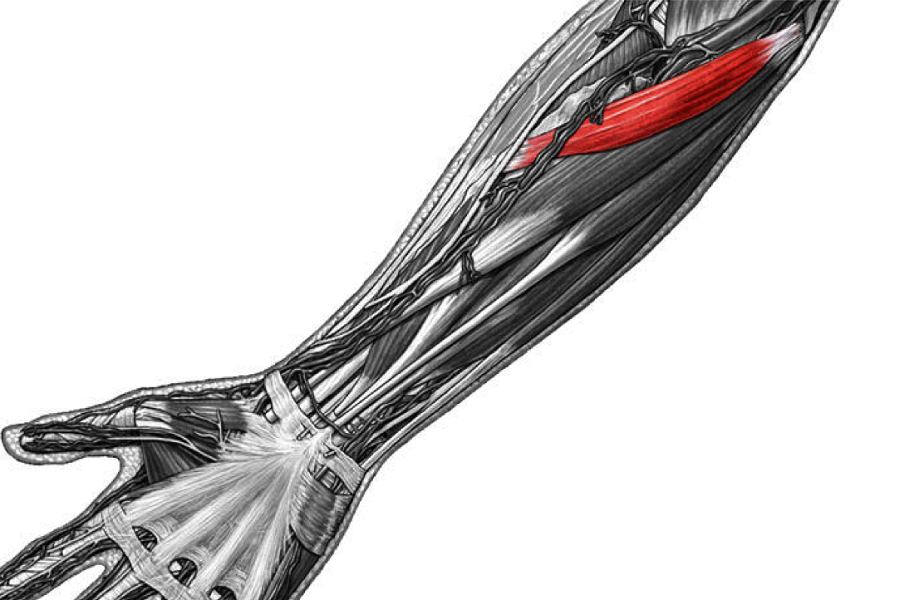

Анатомия и функции мышцы brachioradialis